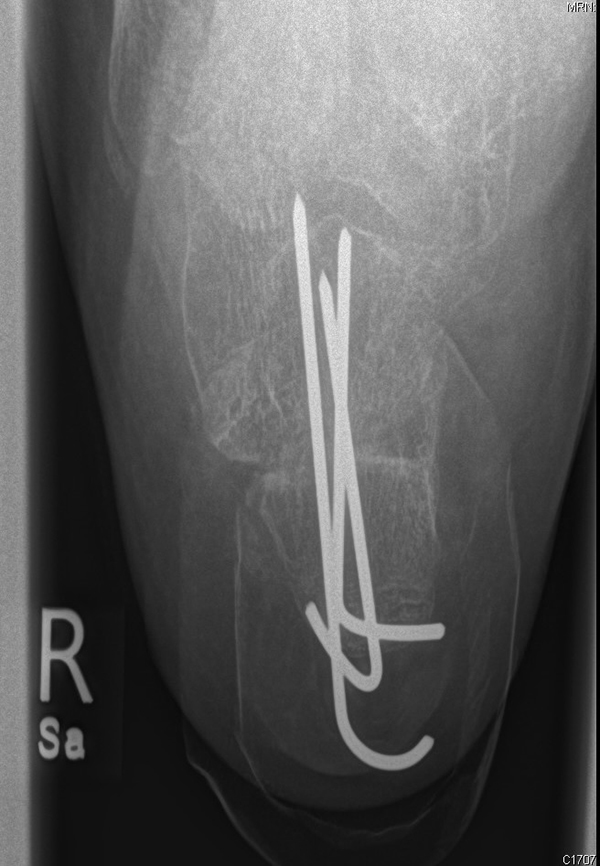

Liegt eine stark subduktische 5. Zehenposition vor, fräsen wir bevorzugt in der Kramertechnik für eine maximale Korrektur und Setzen für zwei bis drei Wochen einen intramedullären Draht nach proximal durch die Osteotomie (Abb. 27).

Abb. 27 a-d: Radiologische Darstellung intraoperativ (a) und vor dem Entfernen des Drahtes einer kompletten Schaftosteotomie mit intramedullärem Draht stabilisiert (b). Die Osteotomie wird minimalinvasiv durchgeführt und der Draht nach der Spülung über den gleichen Hautschnitt einfach in den Schaft hineingeschoben und die Osteotomie darüber stabilisiert. Das Köpfchen kann anschließend je nach Bedarf plantarisiert oder extendiert werden. Radiologische Verlaufskontrolle vor Entfernung des Drahtes (c-d).

Zum Lesen der Bildbeschreibung und zur Vollansicht bitte die Bilder anklicken. Bilder: A. Helmers.

Anschließend kann, falls erforderlich, mit Tape weiter stabilisierend gezügelt werden. Nicht selten verschieben wir um die gesamte Schaftbreite mit guter Heilung des Knochens.